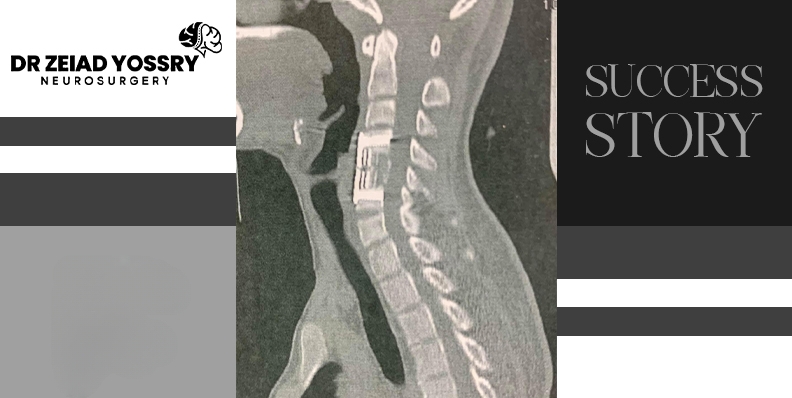

Neck fractures occur at the top of the spinal cord, so their symptoms typically occur in the upper body. However, if the fracture also damages the spinal cord, it can affect the entire lower body. Spinal cord injuries resulting from a neck fracture can be diagnosed through a physical and neurological examination, followed by imaging tests such as an MRI scanning. In this case, the examinations revealed that the fracture in the cervical vertebrae had injured the nerves and caused this young man's quadriplegia, necessitating surgery to repair the fracture.

Surgery was the most appropriate treatment for this young man's case, as the fracture was severe and could not be treated with a neck brace and painkillers. Dr. Zeiad Yossry stabilized the spinal bones and realigned them using plates and screws to align the displaced parts of the fracture or dislocated bones, which helped relieve pressure on the nerves.